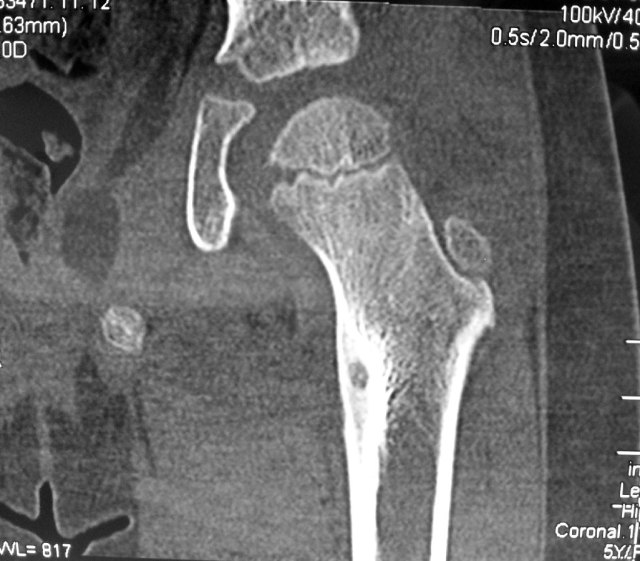

This girl was crying in pain by the time the CT-scans were done. It was obvious that something was wrong. The CT-scan confirmed the presence of an osteoid osteoma of the lesser trochanter of her left hip with pain over her left thigh.

She underwent percutaneous radiofrequency ablation of the tumour under general anaesthesia.

This procedure is done under CT-fluoroscopic guidance.

A 16F needle is inserted through the skin and advanced in a safe zone into the bone of the lesser trochanter under CT-guidance.

The radiofrequency probe is then inserted into the bony tumour.

Correct placement of the radiofrequency probe into the bony tumour lesion is confirmed on CT-scan.

Heat energy is generated by this radiofrequency machine. About 6 minutes worth of energy at 90 degreec Celcius is used to burn the lesion.